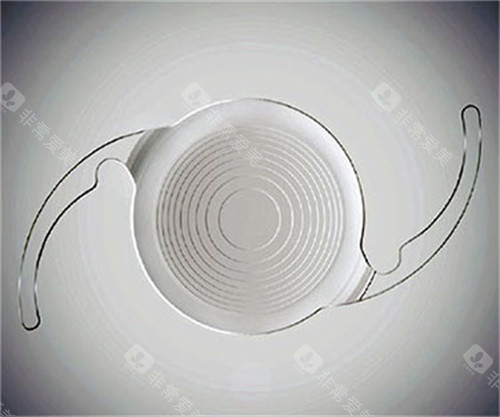

光学干扰:夜间视力的“隐形杀手”

多焦点或散光矫正型人工晶体虽能改善视觉质量,但可能引发眩光、光晕等光学干扰。

尤其在夜间驾驶时,患者可能因灯光周围出现光晕而难以判断路况。一位ICL晶体植入患者反映,术后夜间看车灯时出现明显光晕,需避免夜间出行。

对比敏感度下降:视觉细节的“模糊滤镜”

人工晶体无法完全模拟自然晶状体的调节功能,患者术后可能感觉视觉对比度降低,尤其在暗光环境下难以分辨物体细节。